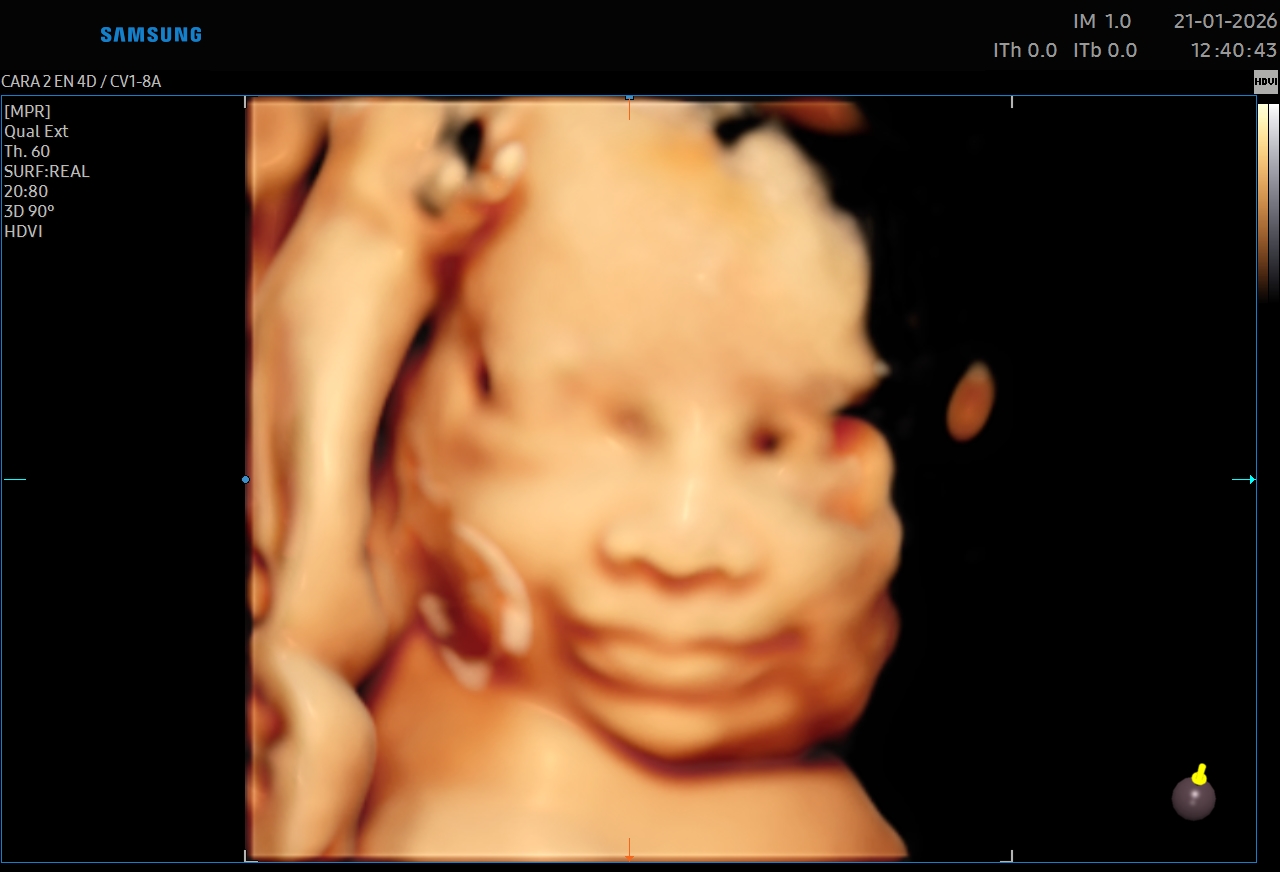

Ecografías 5D

La ecografía 5D es una experiencia única que te permite ver a tu bebé con un nivel de realismo sorprendente, capturando detalles como sus gestos, expresiones y movimientos en tiempo real.

Gracias a esta tecnología avanzada, podrás observar el rostro de tu bebé con mayor claridad, creando un vínculo emocional aún más especial antes de su nacimiento. Es el momento perfecto para compartir con tu familia y guardar recuerdos inolvidables de esta etapa tan importante.

Además de ser una experiencia hermosa, este estudio se realiza con equipos de alta tecnología y bajo supervisión médica, garantizando seguridad tanto para la mamá como para el bebé.